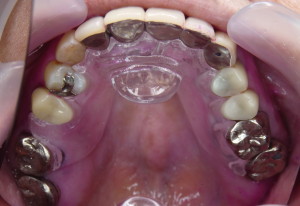

透明だと探す時に困るという訴えで義歯用加熱重合レジンで作ったもの

- 咬合面を覆わないので自由に噛めて、すごく装着感が良く使ってもらいやすい

- 装着しても外観は変わらない、但し「さしすせそ」が発音しにくい